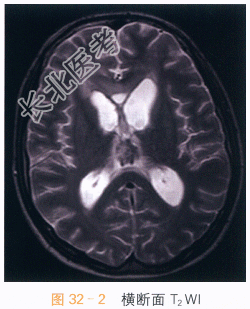

读片分析:头颅横断面T₁WI、T₂WI示松果体区不规则软组织肿块影,呈T₁WI等高、T₂WI低信号影,信号不均匀;横断面、矢状面T₁WI增强扫描可见病灶明显强化,室管膜亦可见明显强化。